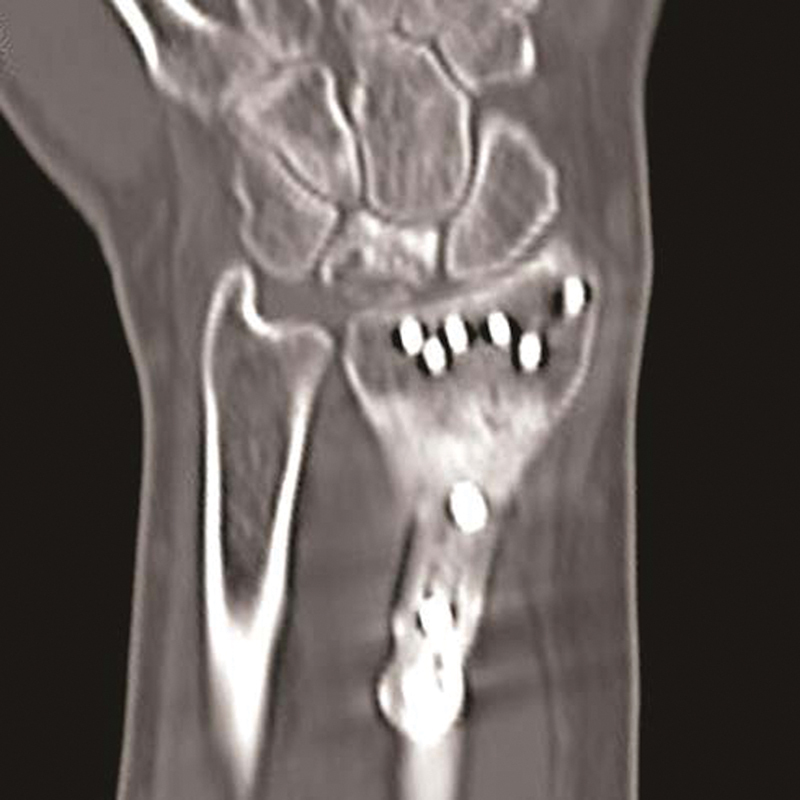

Fig. 1.

Coronal plane fractures not visible on plane radiographs are demonstrated on sagittal computed tomographic images.